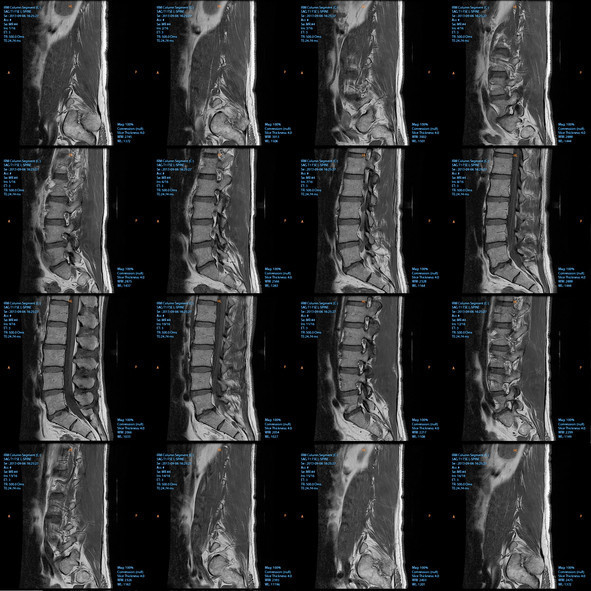

Kauda equina sendromu, omurganın alt bölümündeki sinir demetinin baskı altında kalmasıyla ortaya çıkan nadir ama çok ciddi bir nörolojik acil durum olarak tanımlanıyor. Bu sinirler bacak hareketlerini, his kaybını, mesane ve bağırsak kontrolünü etkilediği için tablo ilerlediğinde kalıcı hasar bırakabiliyor. Uzmanlara göre hastalık tedavi edilmez ya da müdahale gecikirse kalıcı idrar-dışkı kontrol kaybı, cinsel işlev bozukluğu ve bacaklarda felç gelişebiliyor.

Hastalığın en sinsi tarafı, bazen ilk etapta sıradan bir bel fıtığı ya da şiddetli bel ağrısı gibi başlayabilmesi. En yaygın nedenlerden biri alt bel bölgesindeki büyük disk fıtıkları. Bunun dışında travma, omurga darlığı, tümör, enfeksiyon, doğumsal sorunlar ve bazı ameliyat komplikasyonları da tabloyu tetikleyebiliyor.

Bu sendromda zamanla yarışılıyor. Uzmanlar, tanı konduktan sonra sinirler üzerindeki baskının mümkün olan en kısa sürede kaldırılması gerektiğini, ilk 24-48 saatin büyük önem taşıdığını belirtiyor. Tedavi çoğu zaman acil cerrahiyle yapılıyor. Amaç, sinirler üzerindeki basıyı kaldırıp kalıcı hasarı önlemek. Gecikme olduğunda iyileşme şansı düşebiliyor ve bazı hastalarda kalıcı nörolojik sorunlar kalabiliyor.